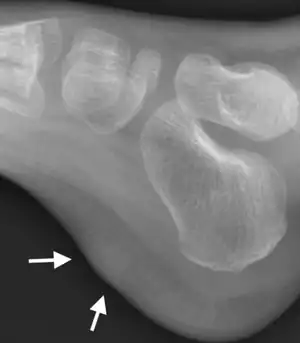

X-ray foot: Fibrous hamartoma of infancy

The diagnosis of FHI is dependent on its presentation as a subcutaneous tumor that often occurs in individuals at birth or ages <1-2 years old; its highly characteristic histopathology consisting of fibroblast/myofibroblast, adipose tissue, and myxoid zones; and its content of tumor cells which have one of the EGFR gene mutations described in the previous section.[4][7] The combination of these factors clearly distinguishes FHI from three recently defined tumors (i.e. fibroblastic connective tissue nevus, medallion-like dermal dendrocyte hamartoma, and plaque-like CD34-positive dermal fibroma[16]) as well as various pediatric spindle-shaped cell neoplasms.[7] Tumor imaging methods such as magnetic resonance imaging may also be helpful in suggesting that a tumor is an FHI.[9][17][18]